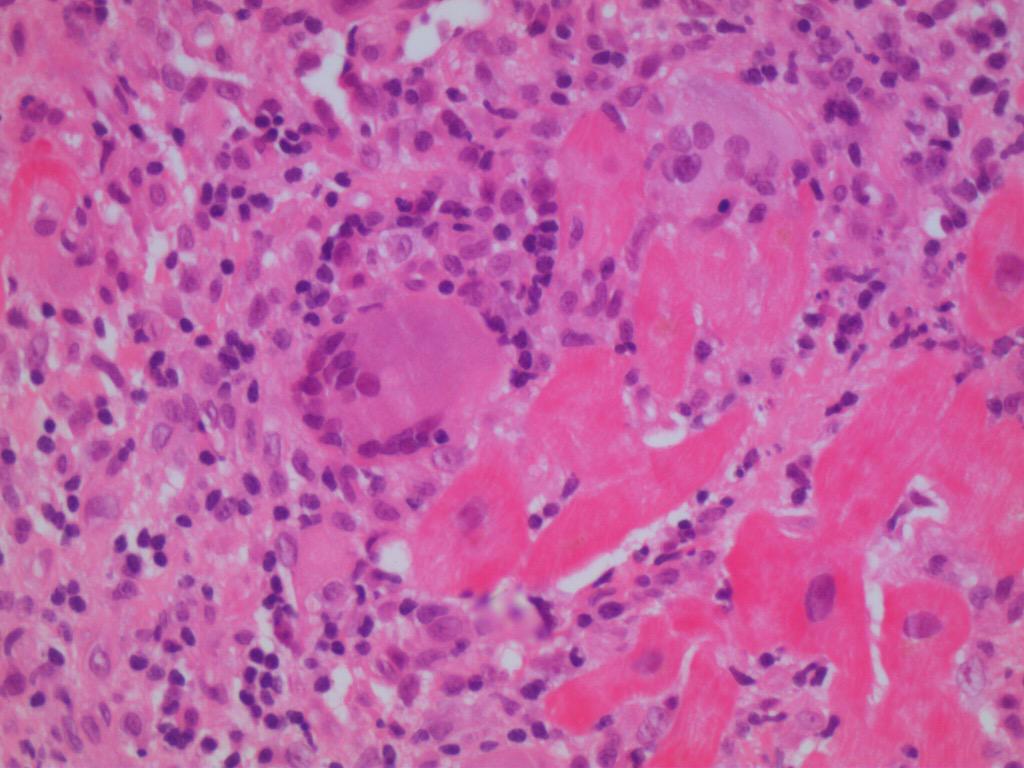

1 diagnostic evaluation of inflammation in a myocardial biopsy specimen (histology and immunohistology). The term 'myocarditis' was first introduced by corvisart it is defined by who / international society and federation of cardiology (isfc) as an inflammatory disease of the heart muscle, diagnosed by established histological, immunological and immunohistochemical criteria Definition / general myocarditis is an inflammatory disease of the myocardium caused by different infectious and noninfectious triggers non infectious types include lymphocytic, eosinophilic and giant cell myocarditis (gcm) Myocarditis may be caused by many disorders (eg, infection, cardiotoxins, drugs, and systemic disorders such as sarcoidosis) but is often idiopathic. Myocarditis is inflammation of the myocardium with necrosis of cardiac myocytes. Myocarditis presents a wide clinical spectrum from sudden cardiac death to an asymptomatic state. J med case reports 4 : Myocarditis can affect your heart muscle and your heart's electrical system, reducing your heart's ability to pump and causing rapid or abnormal heart rhythms (arrhythmias). For the purposes of this study, myocarditis was defined as the presence of an inflammatory infiltrate associated with myocyte injury not due to some other cause, which was present in multiple foci. Dallas criteria myocarditis requires an inflammatory infiltrate and associated myocyte necrosis or damage not characteristic of an ischemic event. 1 diagnostic evaluation of inflammation in a myocardial biopsy specimen (histology and immunohistology). Myocarditis focused myocarditis with stained slides of pathology. Its histological definition by endomyocardial biopsy should be supplemented by immunohistochemistry to identify specific inflammatory cells and polymerase chain reaction to detect viral genomes.

1 diagnostic evaluation of inflammation in a myocardial biopsy specimen (histology and immunohistology). Here, a heart specimen is investigated by microscope for the presence of specific inflammatory cells in the heart, which are normally absent.a clinical classification is also frequently used to in practice. A strategy for the use of cardiac injury markers in the diagnosis of acute myocardial infarction. 1 diagnostic evaluation of inflammation in a myocardial biopsy specimen (histology and immunohistology). Myocarditis can be classified by cause, histology, immunohistology, and clinicopathological and clinical criteria (panel, figure 1).from each categorisation, the treating clinician should consider what information will provide unique prognostic and therapeutic information in a given clinical scenario.

On autopsy, acute (recent onset) myocarditis is characterized by diffuse inflammatory cell infiltration by histology. Symptoms can vary and can include fatigue, dyspnea, edema, palpitations, and sudden death. Subacute myocarditis can manifest as dilation (enlargement) of the ventricles (which pumps the blood out of the heart), thin ventricular walls, and edema (fluid) in the tissues. Definition / general myocarditis is an inflammatory disease of the myocardium caused by different infectious and noninfectious triggers non infectious types include lymphocytic, eosinophilic and giant cell myocarditis (gcm) Primary myocarditis refers to myocardial inflammation in cases in which the primary injury is located within the. 1 diagnostic evaluation of inflammation in a myocardial biopsy specimen (histology and immunohistology). Myocarditis is inflammation of the myocardium with necrosis of cardiac myocytes. 7 traditionally, when the diagnosis was only based upon the histological dallas diagnostic criteria, myocarditis was considered to be a relatively rare cause of heart failure and/or of sudden cardiac death. To establish whether a single myocarditis is a lethal or just an incidental pathology a very careful grading is always mandatory. A strategy for the use of cardiac injury markers in the diagnosis of acute myocardial infarction. While most cases are produced by a viral infection, an inflammation of the heart muscle may also be instigated by toxins, drugs, and hypersensitive immune reactions. Myocarditis presents a wide clinical spectrum from sudden cardiac death to an asymptomatic state. Biomarkers and acute coronary syndromes:

Myocarditis focused myocarditis with stained slides of pathology. Here, a heart specimen is investigated by microscope for the presence of specific inflammatory cells in the heart, which are normally absent.a clinical classification is also frequently used to in practice. The dallas criteria were proposed in 1986 and provided a histopathological categorization by which the diagnosis of myocarditis could be established. Biomarkers and acute coronary syndromes: The term 'myocarditis' was first introduced by corvisart it is defined by who / international society and federation of cardiology (isfc) as an inflammatory disease of the heart muscle, diagnosed by established histological, immunological and immunohistochemical criteria